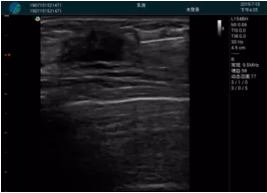

清晰顯示腺體內低回聲快影,邊界清晰,包膜較光滑

確定進針路徑并實時監(jiān)測抽吸針與腫塊位置關系

抽吸針進入腫塊內部進行旋切

抽吸過程中可見腫塊明顯縮小,并根據腫塊位置改變針道位置

抽吸旋切后再進行超聲復查,原腫塊區(qū)域未見殘留組織及出血